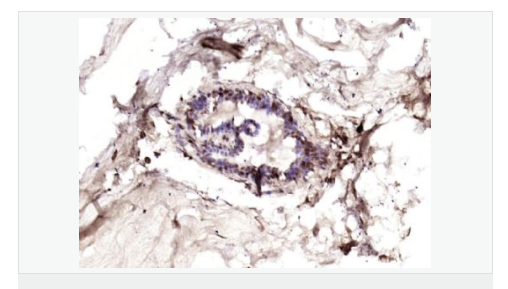

細胞膜受體(Membrane Receptors) c-erbB-4蛋白過去一直為乳腺癌基因研究的主要方向,研究乳腺癌組織學分級及術(shù)后生存期的關(guān)系。目前認為他與細胞增殖活性和激素受體有一定的關(guān)聯(lián),有學者將c-erbB-4蛋白研究用于神經(jīng)內(nèi)分泌蛋白為主。

image.png